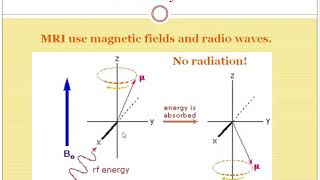

What’s the Difference Between an MRI and a CT? | MRI Vs CT (Clear explanation) What’s the Difference Between an MRI and a CT?

What’s the Difference Between an MRI and a CT? MRI and CT. What is the difference? The MRI Doctor

What’s the Difference Between an MRI and a CT? | MRI Vs CT (Clear explanation) What’s the Difference Between an MRI and a CT?

What’s the Difference Between an MRI and a CT? MRI and CT. What is the difference? The MRI Doctor